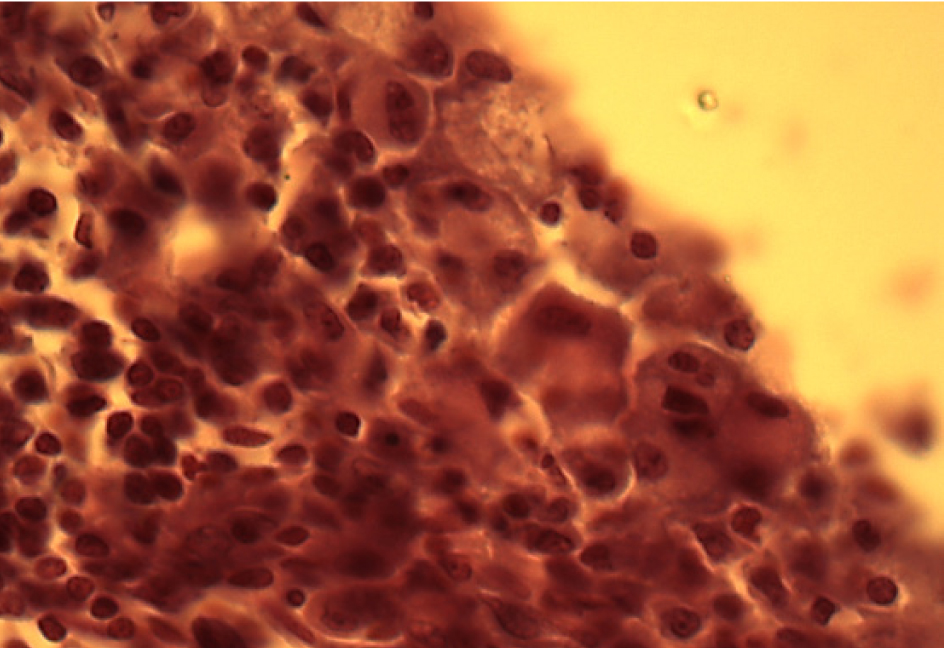

В интерстициальной ткани выявляются скопления многоядерных макрофагов с фагоцитированными частицами фталата свинца, что указывает на выраженную макрофагальную реакцию (рис. 2).

Рис. 2. Скопление крупных многоядерных макрофагов. Окраска гематоксилином и эозином. Ок. 10. Об. 100. Иммерсия

Крупные скопления многоядерных макрофагов в межальвеолярных перегородках легочной ткани свидетельствуют о выраженной макрофагальной реакции. Наличие фибробластов, активно продуцирующих коллагеновые волокна, подтверждает фиброгенные свойства фталата свинца. Присутствие эозинофилов в полиморфноклеточных инфильтратах указывает на способность фталата свинца вызывать сенсибилизацию организма. Все вышеперечисленное является доказательством развития хронических воспалительных процессов.